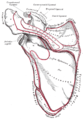

Acromion of left scapula01.png

عظم الكتف الأيسر. صورة أمامية. يظهر الأخرم باللون الأحمر.